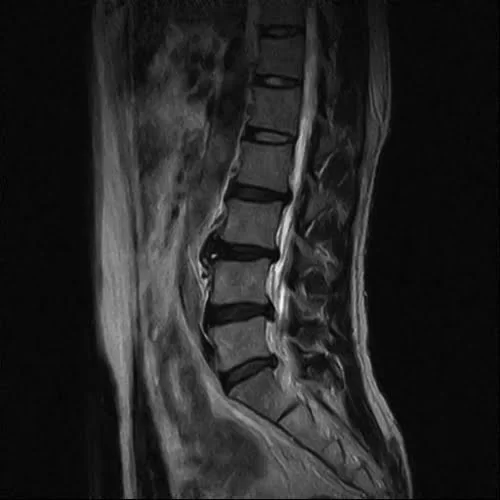

整形外科で撮っていただいたMRIの画像はこれ。

そもそもヘルニアとは?

椎間板ヘルニアに関して簡単に説明すると

こんな感じで骨と骨の間に軟骨があります。

そして腰骨の周りには神経がいっぱい走っているのです。

そんな場所でこんな感じで軟骨が飛び出して神経に触れると

痛みやシビレが出る。それが一般的なヘルニアだと思って下さい。

MRIの検査ではヘルニアの状態が確認出来ているので

誤診ということは無いと思います。

ヘルニアは飛び出した軟骨が神経に触れているから

腰や足に痛みやシビレが出ると言われるのですが。。。

今回のお客様の例で考えると

飛び出した軟骨が施術で元に戻って痛みが消えたのか

そもそも飛び出した軟骨と腰や脚の痛みは関係ないのか

ご判断はお任せいたします。